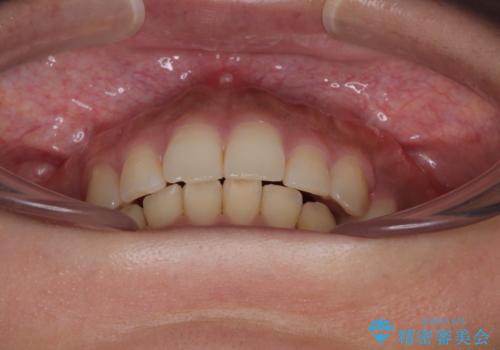

口元の突出感が改善されてことで、下唇に引っかかっていた上顎前歯も気にならなくなりました。

- 前歯のデコボコと口元の突出感を気にして来院された患者様です。

上下前歯がくちばしのように突出していたため、上下左右の第一小臼歯4本を抜歯し、ワイヤー装置にて矯正治療を行うこととしました。